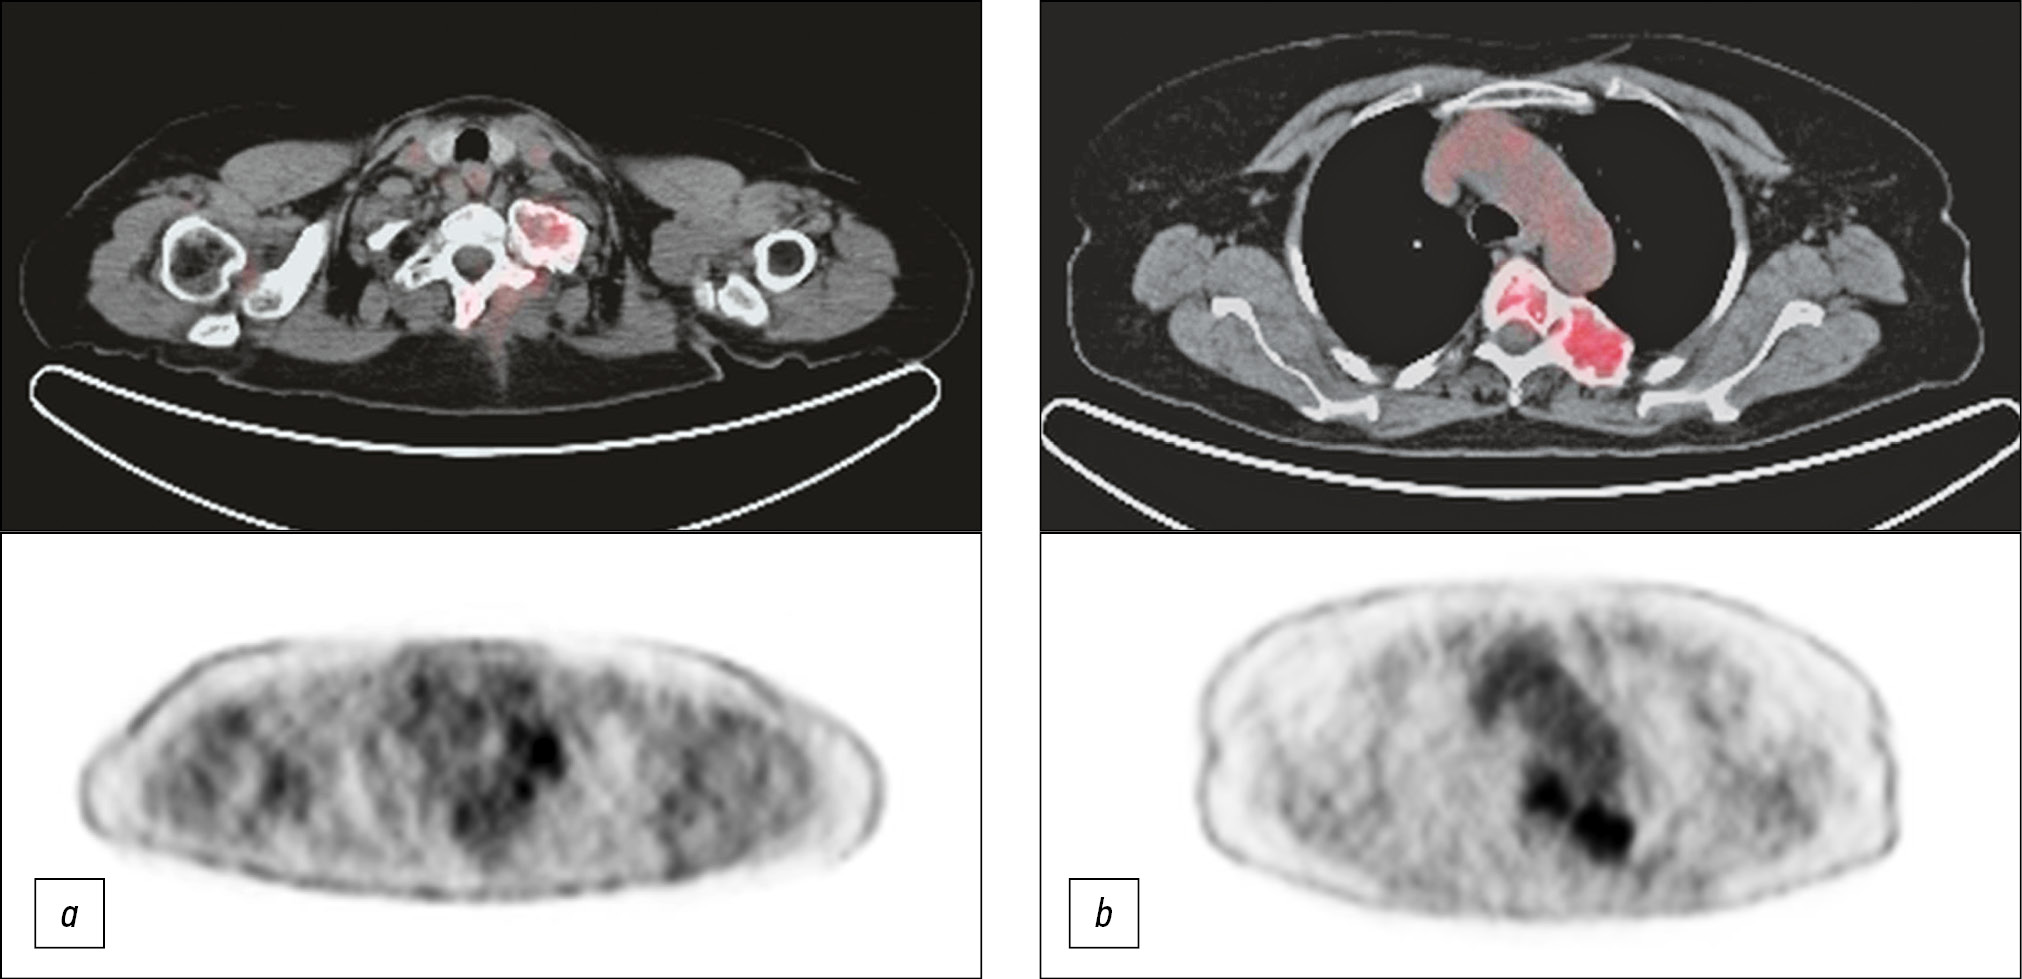

Along with demographic and nosological data that is typical for epidemiological registers, the multimodal data banks consider key clinical and paraclinical data, such as the results of laboratory, morphological, and instrumental research methods, and various imaging methods, such as ultrasound, computed tomography (CT), magnetic resonance imaging, single-photon emission computed tomography/CT, and positron emission tomography/CT. The multimodal data banks present the molecular genetic profile results of the tumor, of which the clinical usefulness in the choice of treatment tactics is undoubted today. All these data are accumulated in the multimodal data banks, noting the execution time and the revision results (second opinion), considering standardized qualitative and quantitative parameters (factors) that potentially affect the clinical course, treatment response, complication development, and outcomes.